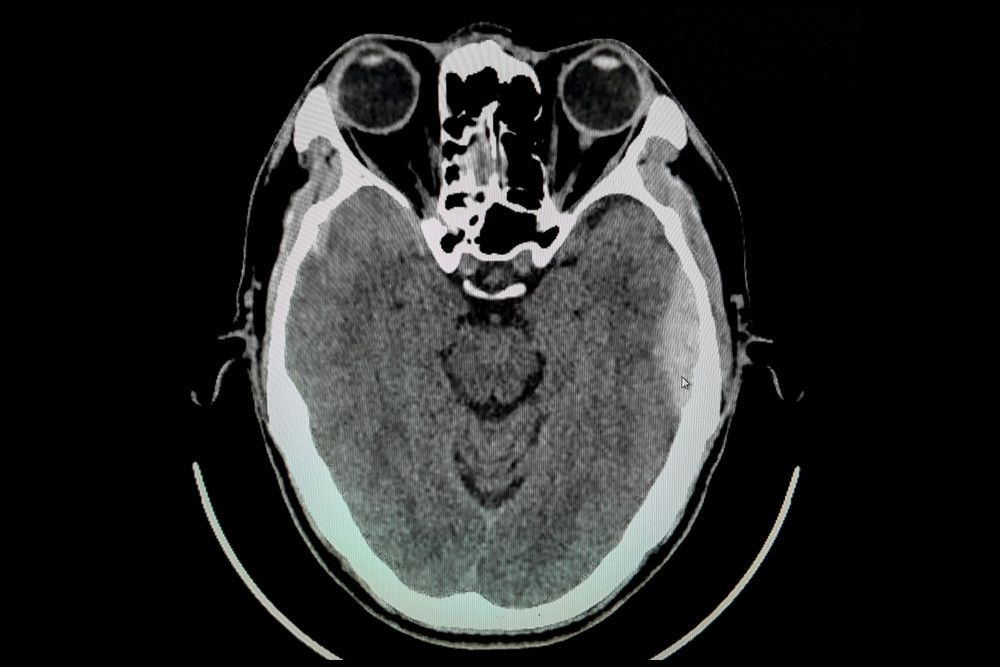

7. Epidural Hematoma

:format(webp)/article/zvdrioe5O48KH4o95Boug/original/069955700_1531449937-Epidural-Hematoma-By-Monet_3k-shutterstock.jpg?w=256&q=100)

Perdarahan otak seperti epidural hematoma juga dapat menyebabkan gejala muntah dan pusing berputar.